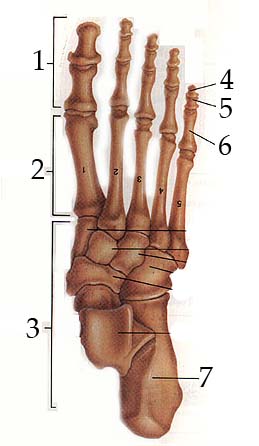

Fig 15.4

1. Phalanges

2. Metatarsals

3. Tarsals

4. Distal Phalanges

5. Middle Phalanges

6. Proximal Phalanges

7. Calcaneus